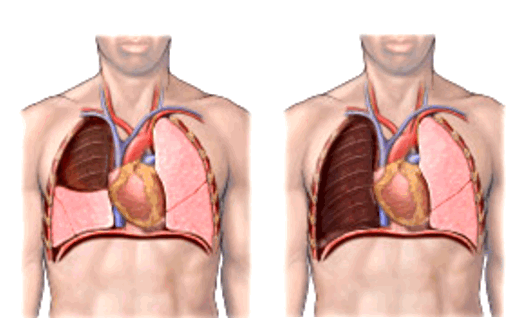

- по объему резекции (лобэктомии (удаление доли легкого), билобэктомии (удаление двух долей легкого), пневмонэктомии (удаление целого легкого)),

Фото 3 — Лобэктомия

Фото 4 — Пневмонэктомия